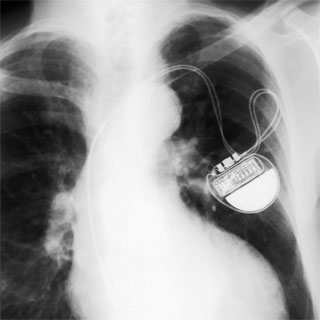

A americana Carol Kasyjanski se tornou, no mês de agosto, a primeira pessoa nos Estados Unidos a ter implantado um marca-passo com conexão sem fio à rede mundial de computadores. Tanto o funcionamento do coração como o do equipamento são monitorados remotamente pelos médicos do hospital St. Francis, de Nova York. Diariamente, é feita uma checagem automática pelo servidor do hospital, para averiguar se há algum problema. O computador é capaz de avaliar se há algo de preocupante, e o médico só é avisado se a máquina detectar algum risco.